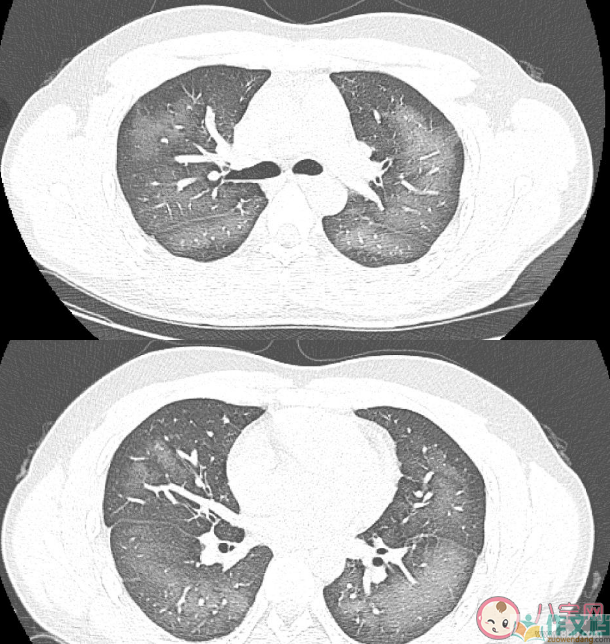

经检查,肺部CT片显示,李林双肺赫然呈现大范围白色样病变,报告提示“白肺”。

除了感染、弥漫性肺泡出血综合征等“白肺”最常见的病因外,吸入有害物质如粉尘、喷雾等,也可导致肺部出现大范围白色样病变。这位年轻的患者就是因为使用不当,吸入了一部分防晒产品进入肺部,导致“白肺”的发生。急诊医生给予吸氧、化痰、抗感染等相关治疗后,李林症状得到明显改善。